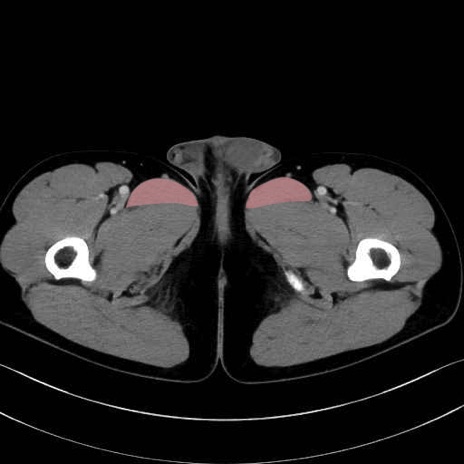

長内転筋(Adductor longus muscle)のCT画像の解剖

長内転筋 (Adductor longus)